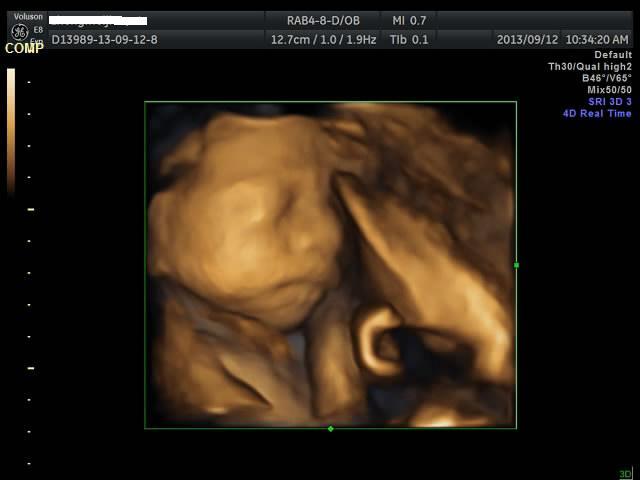

有没有能够帮我看看是千金还是帅哥的朋友?只是好奇是应该准备蓝色衣服还是应该买粉色衣服呢? 点击展开 匿名用户 2013-09-12 20:44 为您推荐: 其他回答 吓死我了... 匿名用户 2013-09-12 20:57 看不出来啊,买米黄色的吧 不论男女,都很好看 匿名用户 2013-09-12 20:57 帅哥的朋友吧,最好选粉红色的 匿名用户 2013-09-12 20:53 要怎么看才好 匿名用户 2013-09-12 20:48 千金,买粉红的 匿名用户 2013-09-12 20:47 相关问题 谁帮我看看是千金还是帅哥! 来看看我家24天的小帅哥,穿粉色衣服么么哒 张凡帅吗?很好奇听说是个帅哥,求解!!!!!!!